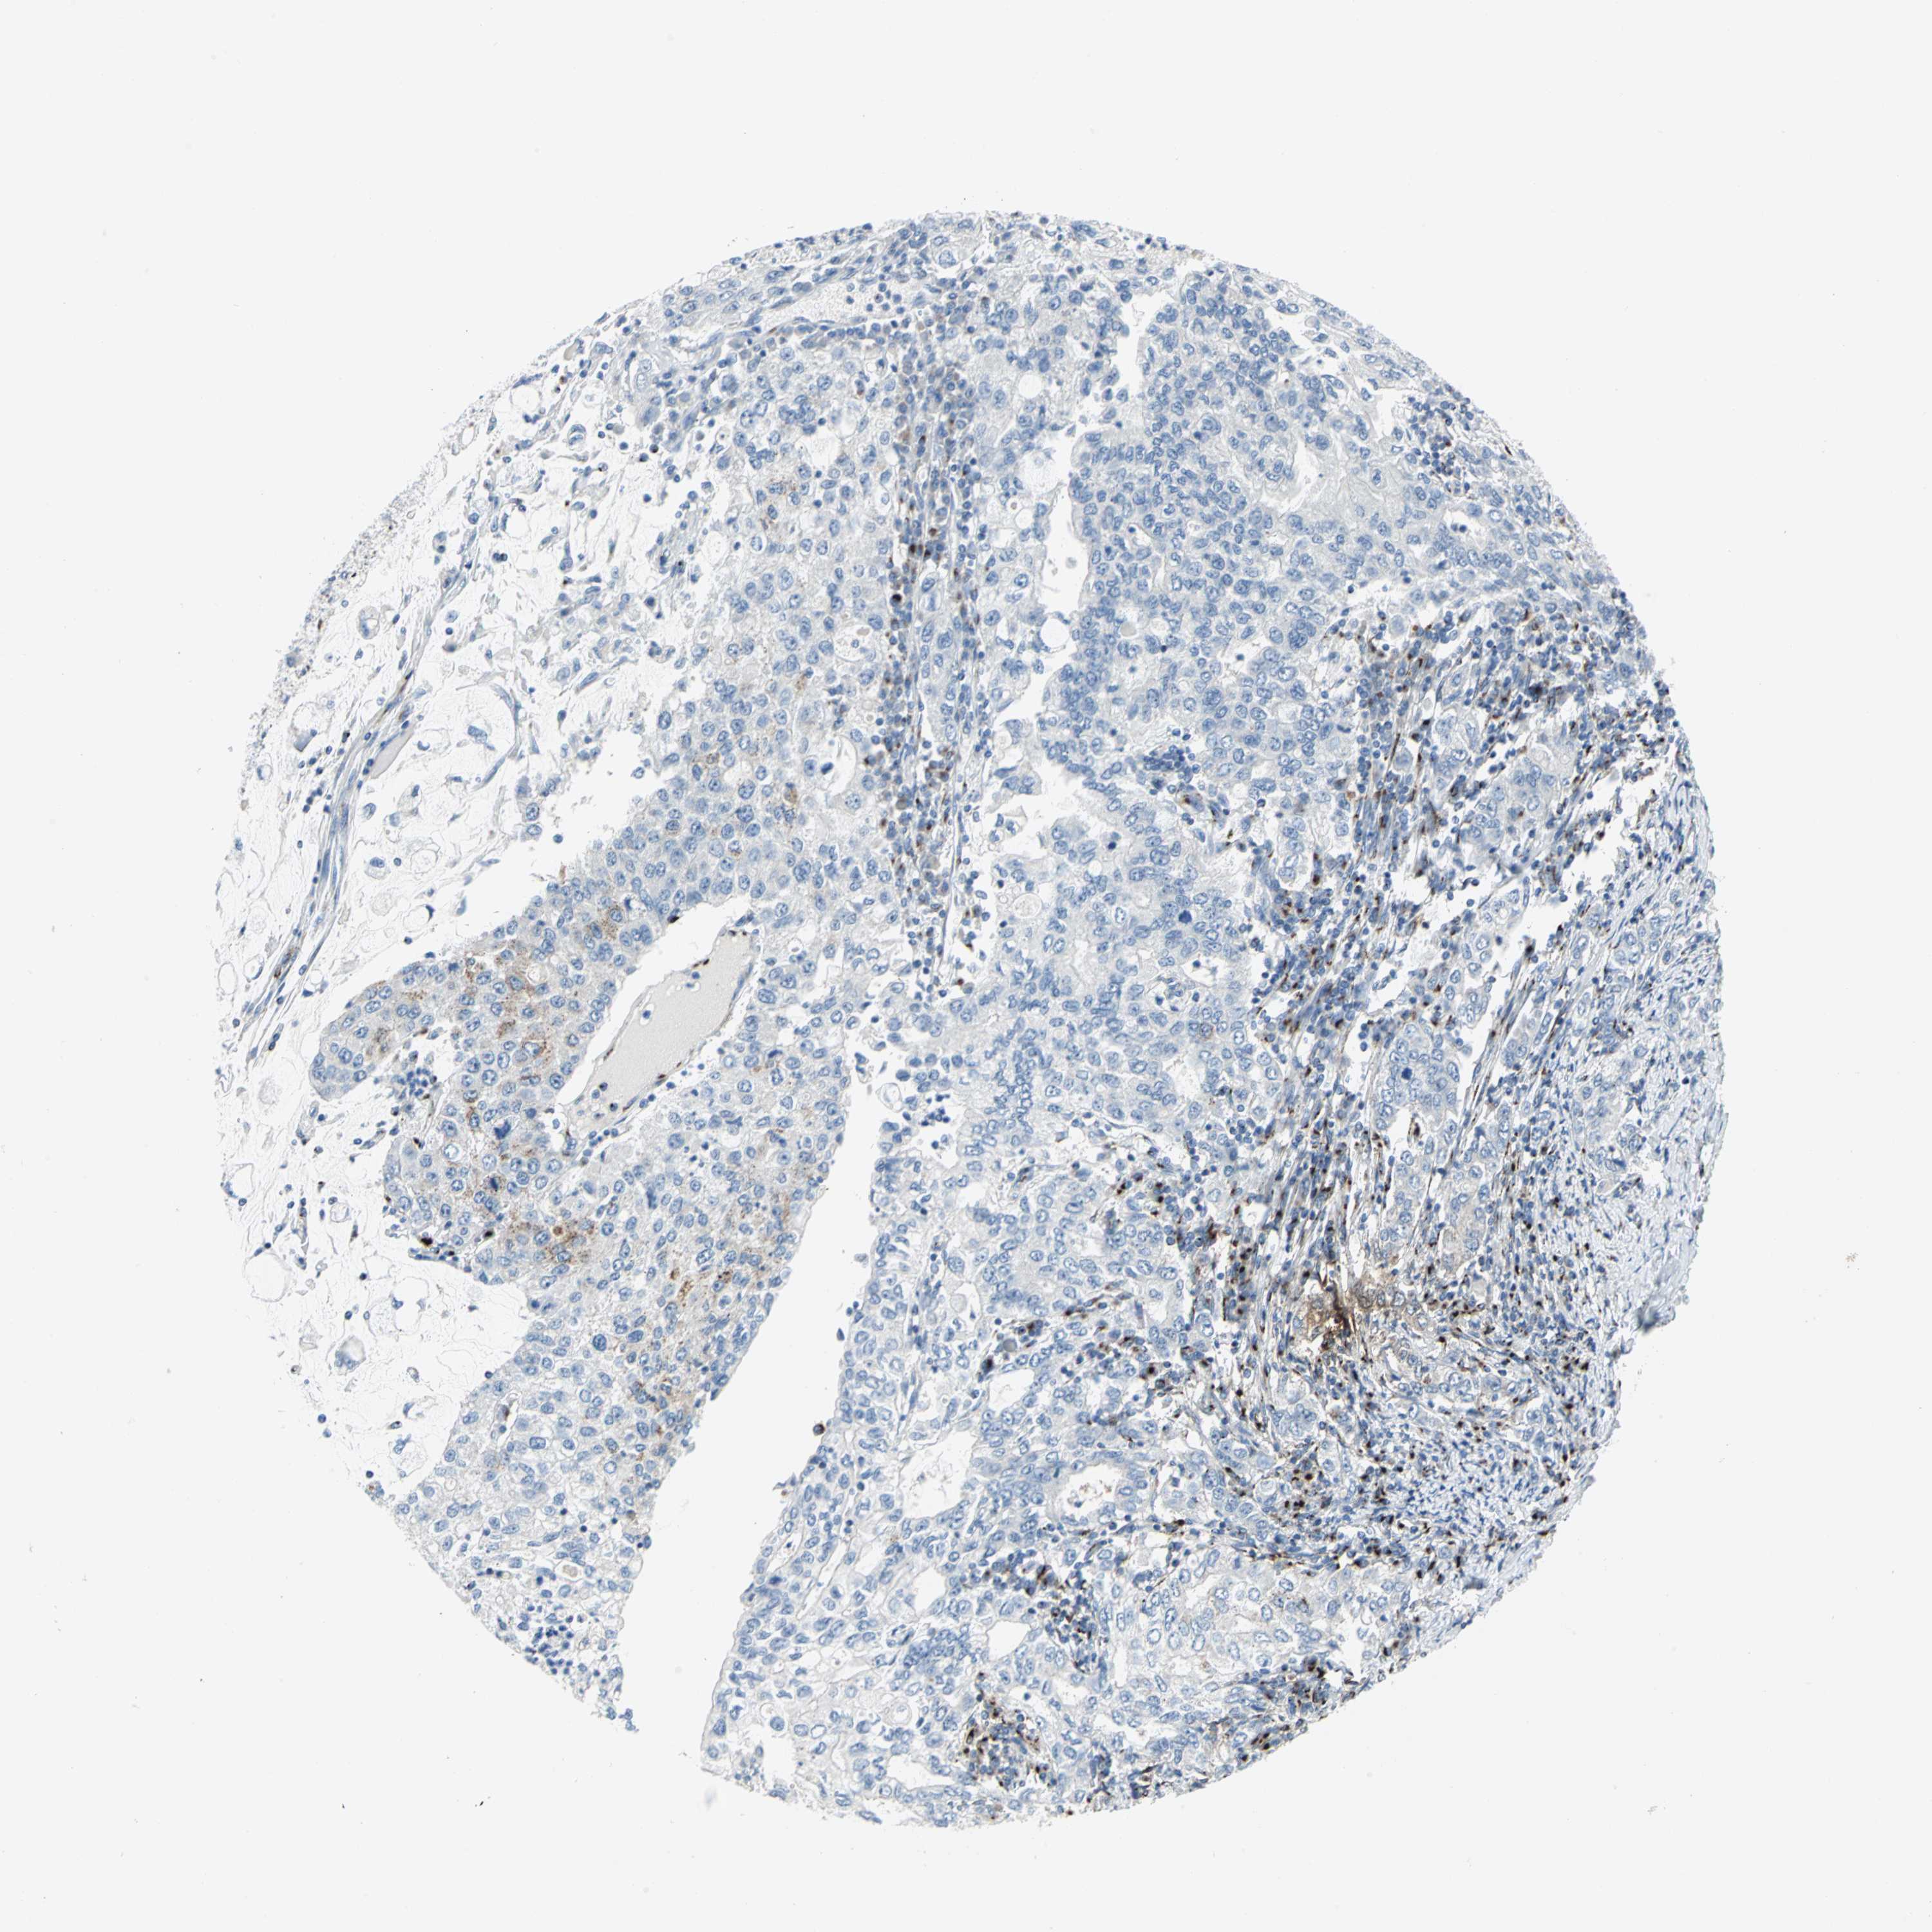

STOMACH CANCER - Protein expressioni

A mouse-over function shows sample information and annotation data. Click on an image to view it in a full screen mode. Samples can be filtered based on level of antibody staining by selecting one or several of the following categories: high, medium, low and not detected. The assay and annotation is described here.

Note that samples used for immunohistochemistry by the Human Protein Atlas do not correspond to samples in the TCGA dataset.

Antibody stainingi

Antibody staining in the annotated cell types in the current human tissue is reported as not detected, low, medium, or high, based on conventional immunohistochemistry profiling in selected tissues. This score is based on the combination of the staining intensity and fraction of stained cells.

Each image is clickable and will lead to virtual microscopy that enables deeper exploration of all samples and also displays staining intensity scores, fraction scores and subcellular localization as well as patient and tissue information for each sample.

Antibody CAB006254

Staining

High

Medium

Low

Not detected

Intensity

Strong

Moderate

Weak

Negative

Quantity

>75%

75%-25%

<25%

None

Location

Nuclear

Cytoplasmic/membranous

Cytoplasmic/membranous,nuclear

Adenocarcinoma, NOS

Adenocarcinoma, High grade